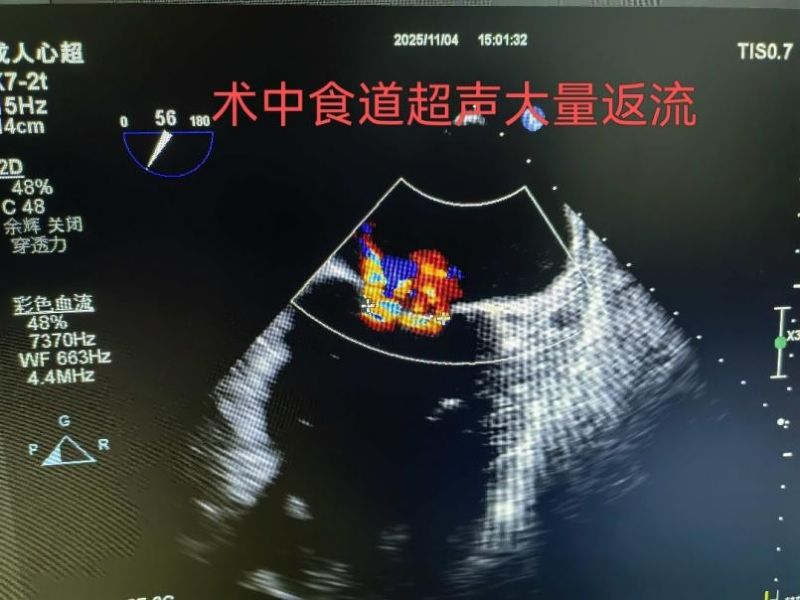

患者文先生5年前曾患急性心肌梗死,此后反復(fù)出現(xiàn)胸悶、氣短癥狀,活動(dòng)能力逐年下降。入院檢查顯示,其心臟射血分?jǐn)?shù)(EF)僅為39%(正常范圍50%-70%),二尖瓣返流面積達(dá)13.4cm2,左心房擴(kuò)大至74mm,傳統(tǒng)外科手術(shù)風(fēng)險(xiǎn)較高。經(jīng)心血管內(nèi)科、心臟外科等多學(xué)科會(huì)診后,醫(yī)療團(tuán)隊(duì)推薦采用TEER技術(shù)進(jìn)行治療。主管醫(yī)生王銀濤就“經(jīng)導(dǎo)管二尖瓣緣對緣修復(fù)術(shù)(TEER)”與家屬達(dá)成意向。

手術(shù)于11月4日下午進(jìn)行,通過股靜脈穿刺送入夾合器,在食道超聲實(shí)時(shí)引導(dǎo)下,精準(zhǔn)植入2枚瓣膜夾修復(fù)二尖瓣。整個(gè)過程歷時(shí)約2小時(shí),術(shù)中出血量僅50ml。術(shù)后次日,患者即可下床活動(dòng),復(fù)查顯示EF提升至46%,二尖瓣返流面積縮小至3.0cm2,左心房縮小至66mm,胸悶、氣短癥狀明顯緩解。

2.精準(zhǔn)定位:在食道超聲和X線引導(dǎo)下,將夾合器送達(dá)二尖瓣位置,通過夾合病變瓣膜減少返流;